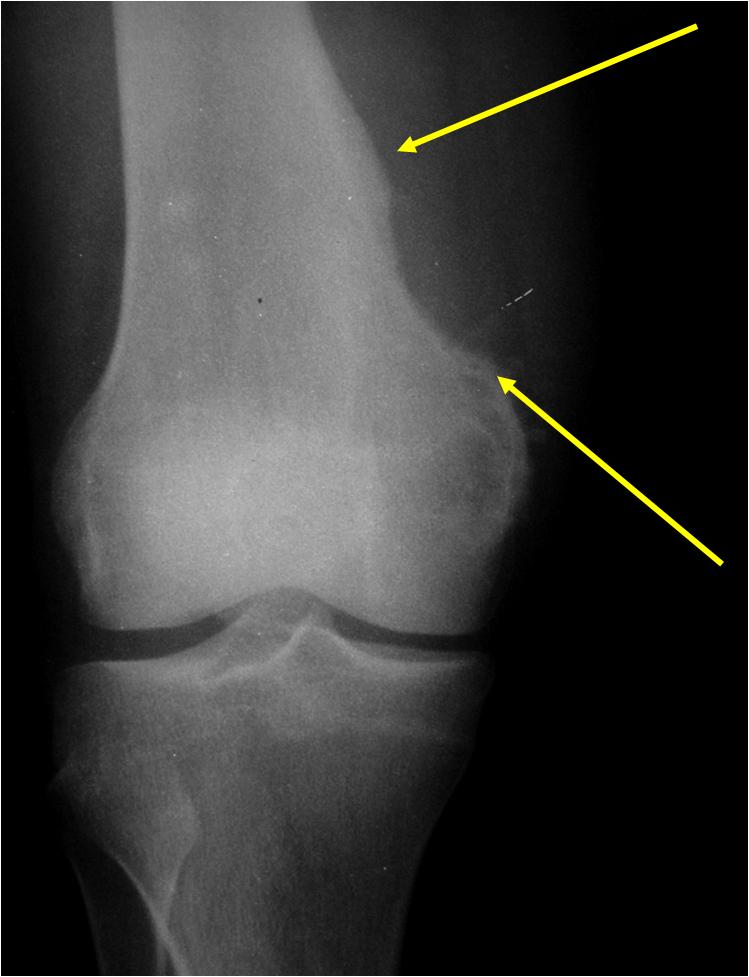

Radiology:

- Metaphyseal

- Cortical erosion with sclerotic underlying cortex (saucer shaped defect)

- Matrix calcification

- Triangular sclerotic spur at margin of tumor

- >5cm in diameter; average size: 11 cm (vs periosteal chondroma that is usually <5cm)

- No hair on end periosteal reaction (vs. chondroblastic osteosarcoma)

- Intramedullary canal is spared

(Bottom Arrow) Erosion of Outer Cortex